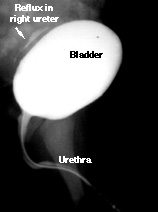

This child has vesicoureteric reflux. Notice the contrast material filling the right ureter. The contrast does not fill the renal pelvis. Fortunately, this boy has rather mild reflux (grade I on a scale of I - VI).

See an example of more severe reflux.